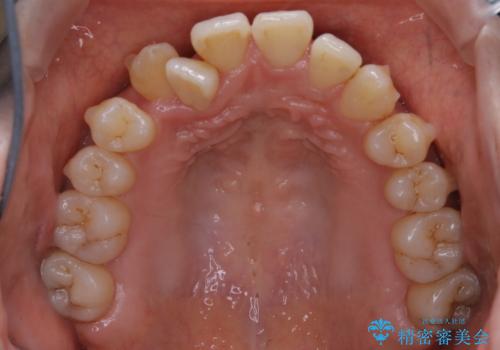

本来は外科ケース:インビザラインで前歯の重度がたつきとオープンバイトの改善

- 前歯のがたつきが気になるとご相談にいらした患者様です。矯正検査の結果、骨格的なズレが大きかったため当初の治療計画では外科矯正をご案内しました。ご本人が手術を望んでおらず、可能な限りの改善を目指すことを目標に治療を開始しました。

元々の骨格的なズレが大きかったため、当初は外科矯正をご提案していました。患者様の強いご希望により、非外科的な処置のみで可及的な改善を目指すことを目標に治療を行いました。以前よりもしっかり噛めるようになり、見た目も劇的に改善したことで大変ご満足いただけました。